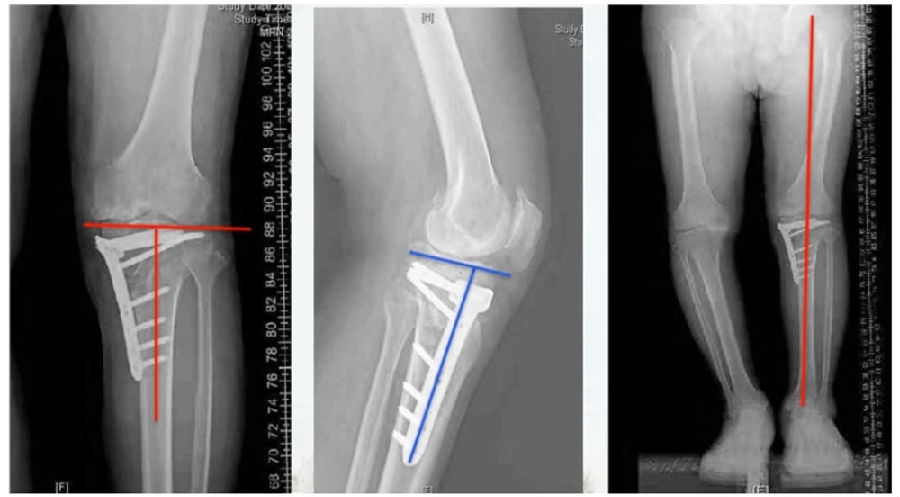

典型病例,女性,56岁,农民右膝内翻18度。

术前影像

术中影像

结合影像学来看,该患者单纯用闭合截骨或开放截骨,对肢体均有影响,所以决定采用混合型截骨。术中混合截骨旋转中心选在内外1/3处,先做闭合楔,然后顺势将开放楔敲开,达到术前设计的目标力线。术后随访力线达到要求。

术后X线